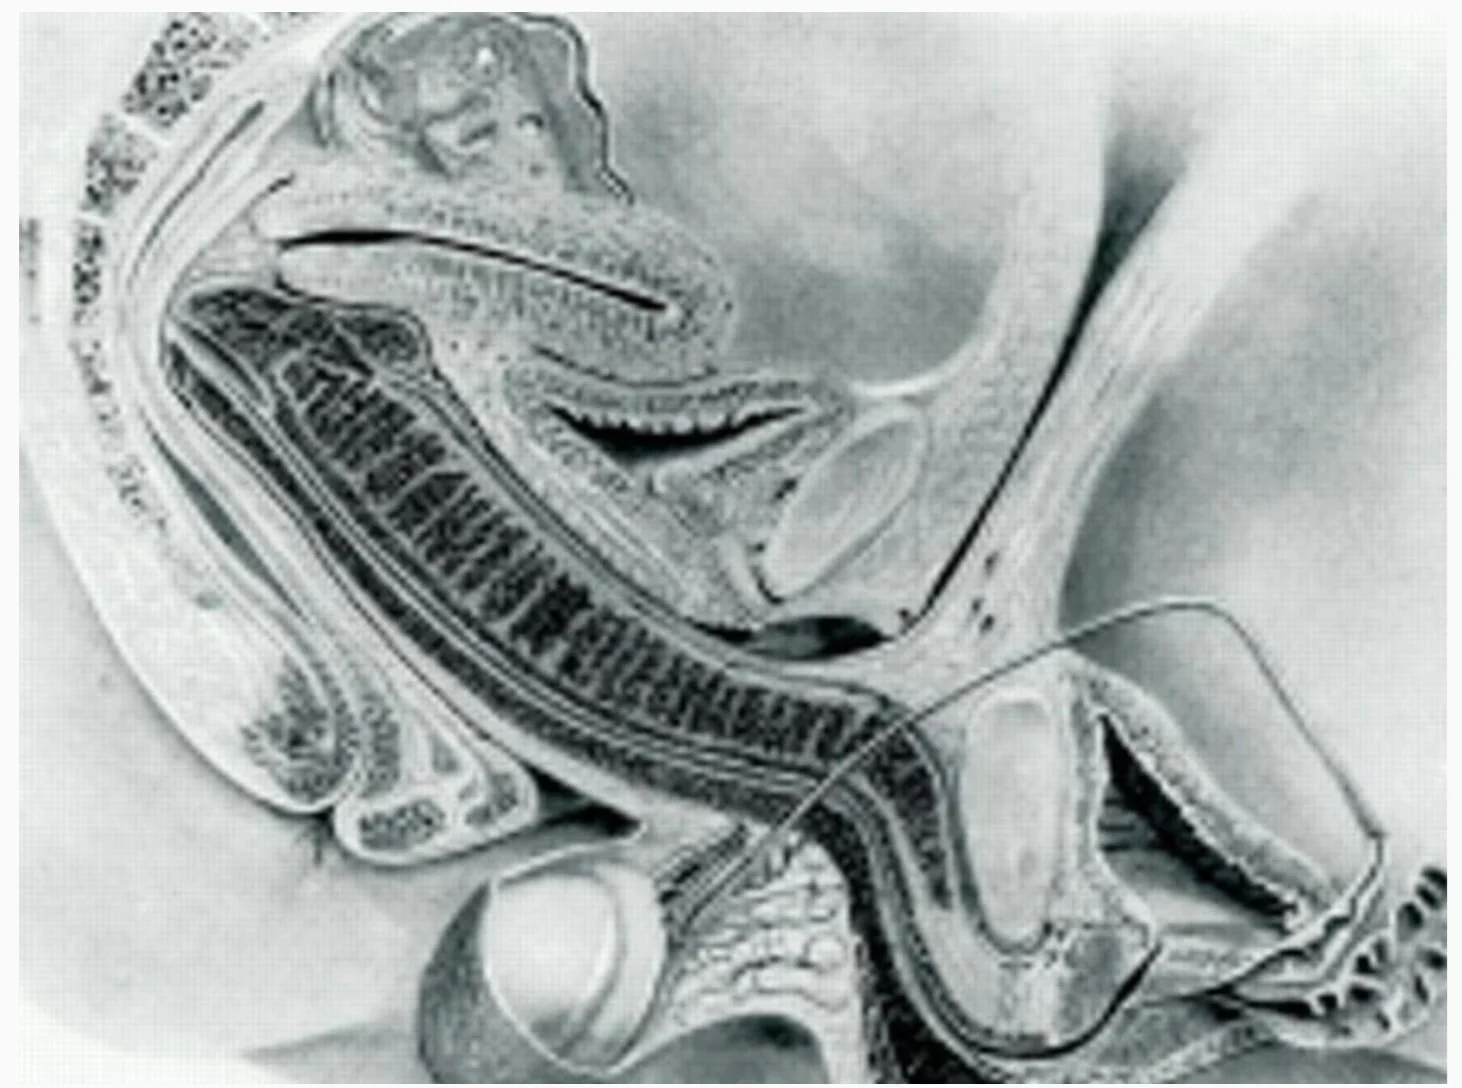

Η πιο σημαντική διαπίστωση της μελέτης αφορά το σχήμα του ανδρικού μορίου. Μέχρι τότε, η επικρατούσα θεωρία ήθελε το πέος να παραμένει ευθύ ή σε σχήμα “S”. Οι εικόνες από τον μαγνητικό τομογράφο όμως έδειξαν κάτι εντελώς διαφορετικό.

Το σχήμα μπούμερανγκ: Κατά τη διάρκεια της διείσδυσης στην ιεραποστολική στάση… Το ανδρικό μόριο καμπυλώνεται σημαντικά για να προσαρμοστεί στη φυσική κλίση του κόλπου.

Η ρίζα του πέους: Αποκαλύφθηκε ότι περίπου το 1/3 του συνολικού μήκους του οργάνου βρίσκεται εσωτερικά στο σώμα, αποτελώντας τη «ρίζα» που του επιτρέπει αυτή την ευελιξία.

Προσαρμογή του κόλπου: Ο γυναικείος κόλπος δεν είναι ένας ευθύς σωλήνας, αλλά αλλάζει σχήμα και έκταση… Με τη μήτρα να ανασηκώνεται μάλιστα κατά τη διάρκεια της διέγερσης.